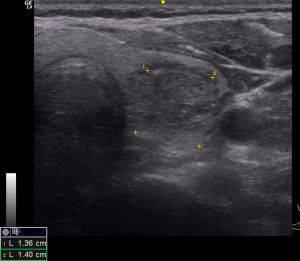

A thyroid nodule is a radiologically distinct entity that appears different to the surrounding thyroid parenchyma usually on ultrasound scan. Nodules can be solid, cystic or a combination of these. Cystic portions are anechoic on ultrasound and they appear black with through transmission of ultrasound appearing bright at the far edge of the cyst whereas solid portions have varying degrees of echogenicity making them appear different shades of grey through to black.

Ultrasound is a highly accurate investigation for looking at the details of a nodule and for assessing its risk for being a cancer. There are several scoring systems that have been devised to identify the degree of risk and which nodules should be recommended for Fine Needle aspiration (FNA) biopsy, observation or no follow up. The one in wide use in Auckland is The TIRADS system from the American College of Radiology (ACR). This system scores thyroid nodules based on shape, margin, echogenicity, density , and whether there are calcifications within the nodules. Scores range from TR1 (benign) through TR6 (biopsy proven malignancy) and then size is used to make recommendations regarding FNA. An online TIRADS Calculator makes this an easy system to utilise. A nodule with a TIRADS score of TR5 that is over 1cm in size should have a FNA similarly a nodule that Scores TR3 should only have FNA if it is >2.5cm and should be followed if it is >1.5cm.

A TIRADS TR5 thyroid nodule that is solid, hypoechoic, Taller than wide, Has an irregular margin and contains punctate echogenic foci (PEF) it is over 1 cm in size and biopsy is recommended.

TIRADS TR3 nodule that is isoechoic, spongiform, wider than tall shape, has an irregular margin and no calcifications. As it is >1.5cm (in vertical dimension not shown) observation is recommended.